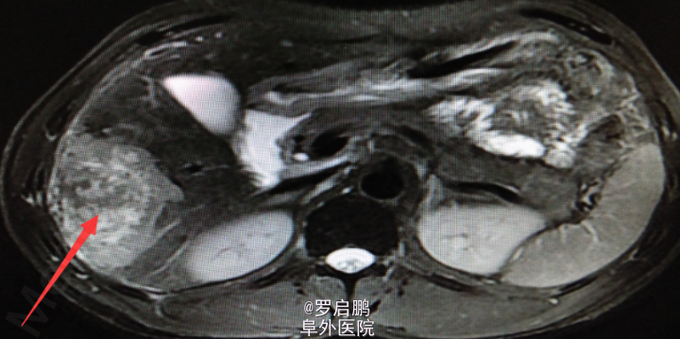

患者 男 48岁 主诉:发现肝脏占位半月 现病史:半月前患者因慢性乙型肝炎复查腹部超声发现右肝占位 既往:慢性乙肝20年,未规律治疗。 个人史:吸烟史25年20支/天,饮酒史13年,白酒2两/次。

超声:右肝高回声光团,胆囊、肝内外胆管、脾脏、双肾未见异常 腹部MRI:肝右叶占位 腹部平扫+增强:肝右叶占位,肝内多发小密度,左肾囊肿,腹膜后淋巴结肿大

肝右叶占位,肝癌? 前入路右半肝切除,LC 鉴别诊断:原发性肝癌;肝转移癌;肝海绵状血管瘤;肝腺瘤;血管平滑肌脂肪瘤。

注意术中循环维持,备血、血浆。术中平稳。术中病理:(右半肝)低分化胆管腺癌,可见坏死,肝内可见多发卫星灶,紧邻肝被膜,切缘未见特殊。术后恢复良好出院。